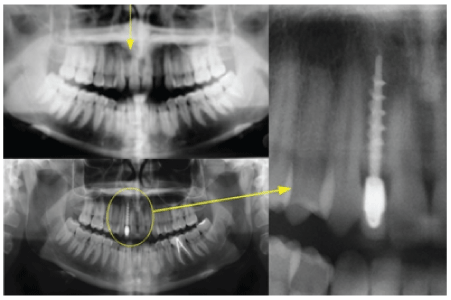

这份报告大约是13岁。男性患者,白种人,双侧第一类磨牙(2.1 1.2)两侧侧切牙发育不全,健康状况良好。他的咬痕很深,导致中央组的横向直径显著减少。

因此,以上图片证明了Invisalign®正畸治疗如何确保获得更多的空间。在本例中,治疗从2011年5月持续到2014年4月,总共使用90个对准器,共获得4.9 mm的空间作为1.2和2.2的空间。

无牙状态的特点是除了明显的骨萎缩外,可用空间很少。为了修复缺失的牙齿,我们最终采用了贵金属合金和陶瓷(Ivoclar Vivadent InLine®)冠(图1-8)来完成上述过程。

图1:年轻男性患者双侧发育不全。可以观察到中切牙和犬齿之间缺乏空间。

图2:正畸治疗后为保守插入种植体所获得的空间。

图3:x线片:1显示剩余骨体积。帕斯夸里尼自定心毛刺,它可以使截骨隧道特定的植入物。手术结束时两颗双皮质螺钉(尖顶内3.5 mm)。